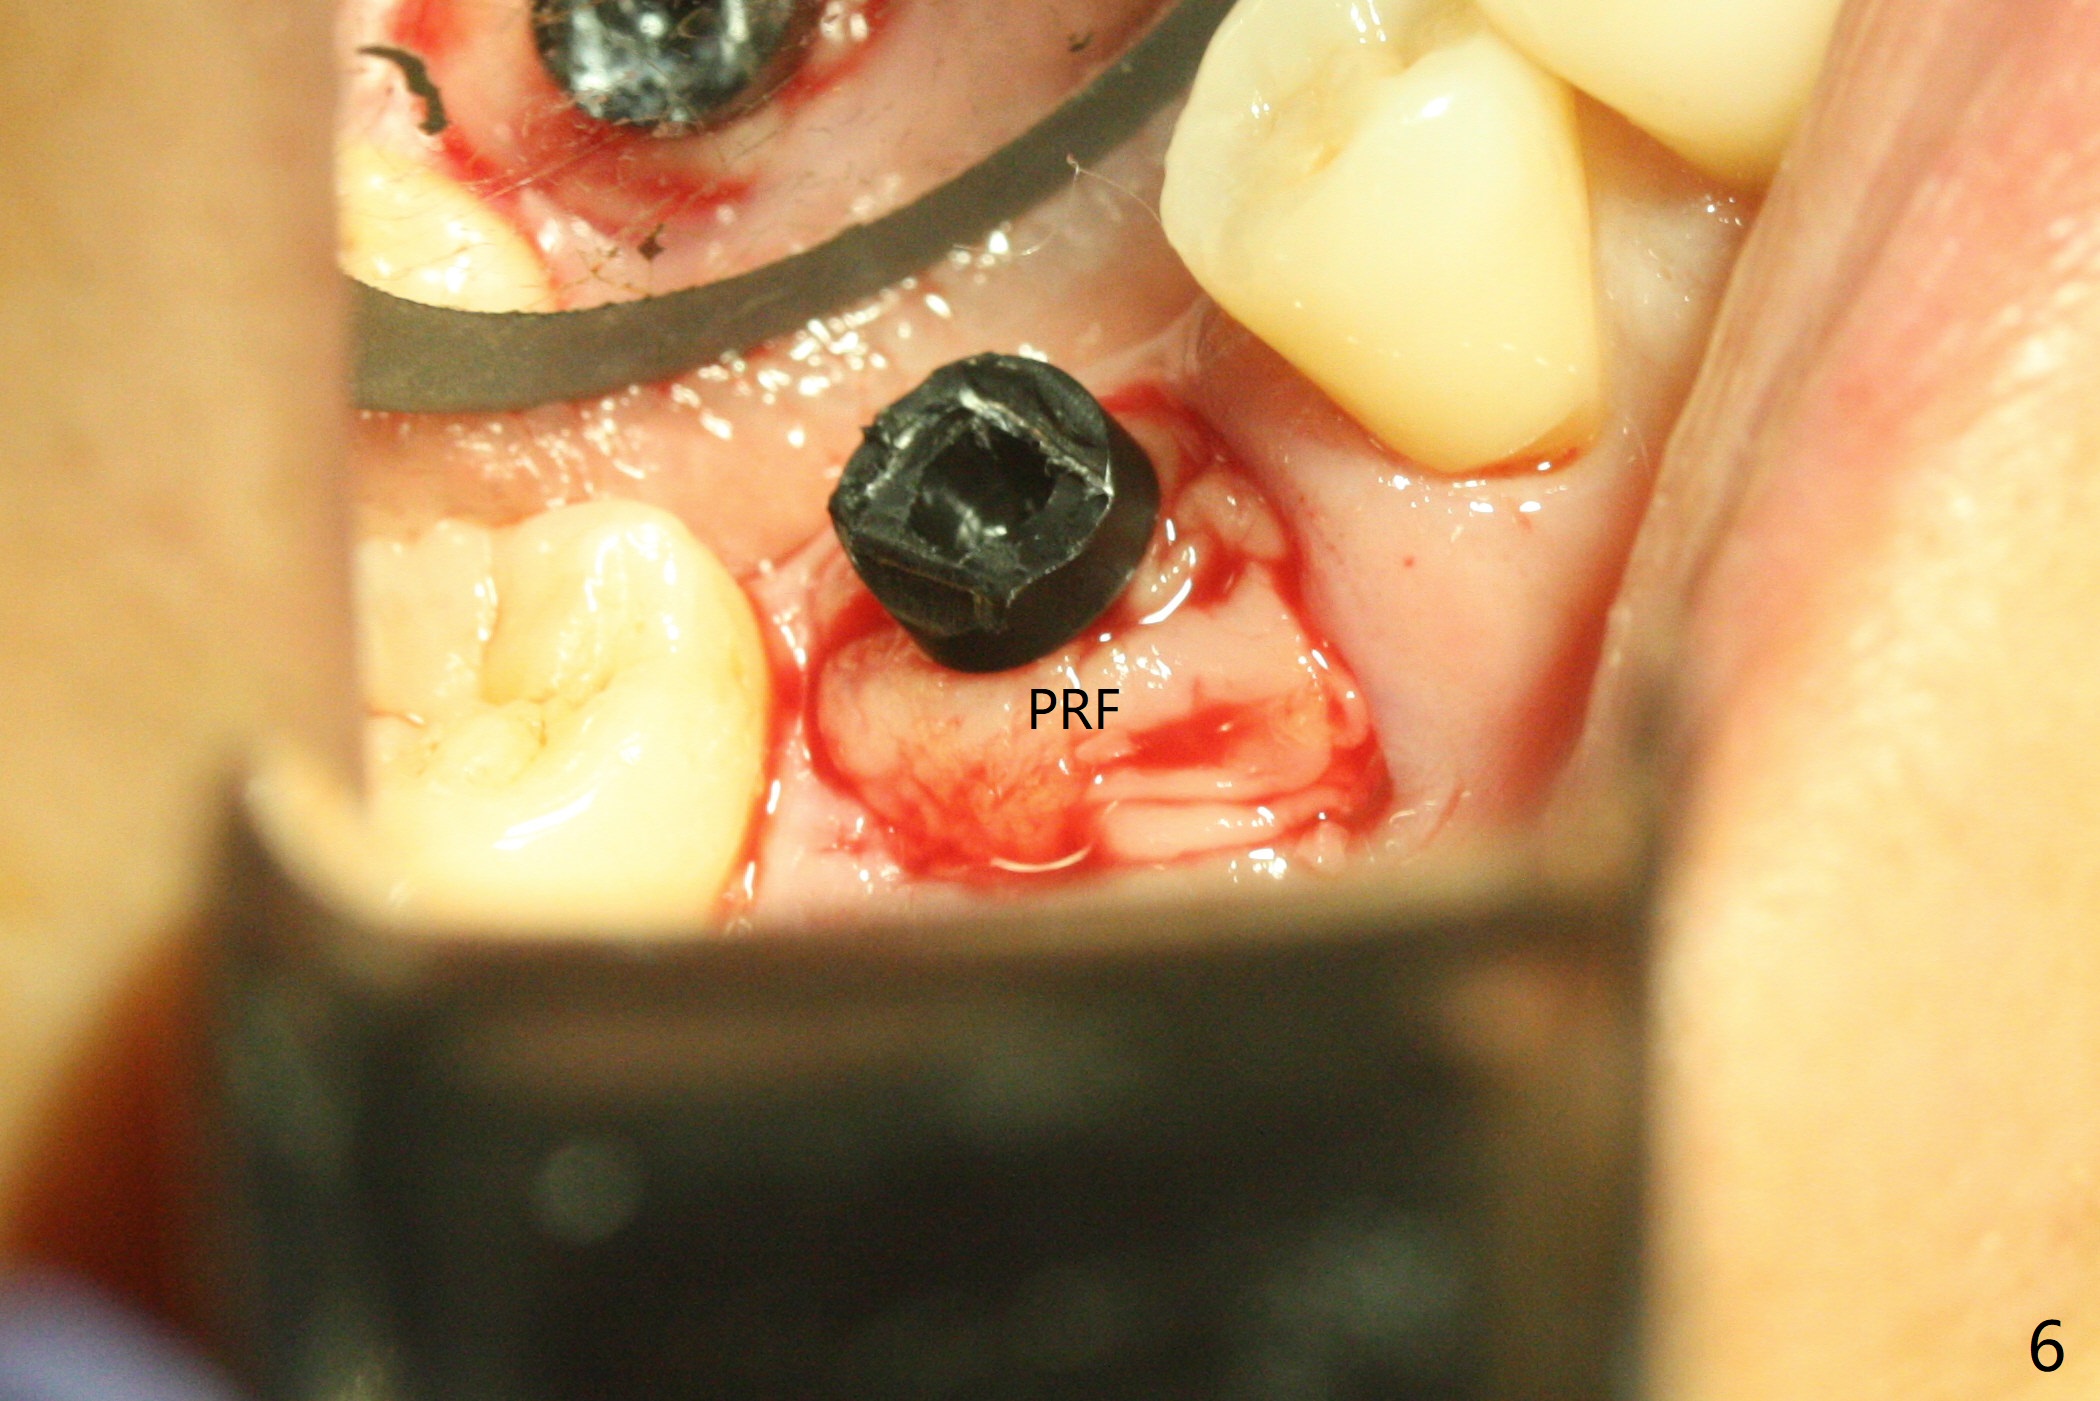

To prevent further postop buccal gingival recession at #30, socket shield is formed with removal of the residual roots (Fig.1,2 *). Osteotomy is initiated in the septum (Fig.2 S, to be flattened with bone trimmer and surgical round bur) and gradually slides slightly into the mesial socket in spite of using surgical guide (Fig.3 *: sleeve). Following 4.5x11.5 mm drill, a 4.5x8 mm Bicon implant is pressed fit; its stability is lightly enhanced with placement of sticky bone in the remaining sockets (Fig.4 *) and around the black plug (Fig.5 P). After removing the coronal portion of the plug to reduce occlusal interference, two pieces of PRF are wrapped around the remaining plug (Fig.6). The main stability of the implant is obtained when setting acrylic (A in Fig.7) is applied into the edentulous space (undercut). After acrylic setting, flowable composite (*) is added distal for further retention. One month postop, the flowable composite is detached. The provisional is sectioned; the black plug is cut. The socket heals with exposure of the mesial socket shield (Fig.8 >). The black healing plug and the mesial socket shield remains exposed 3 months postop (Fig.9). When a 4.5x6.5 mm temporary abutment is placed, the buccal gingiva is blanched and the mesial socket shield is pushed buccal (Fig.10). The implant appears to remain covered by the bone 3 months postop (Fig.11). Cortical bone starts to form crestal 7 months postop (Fig.12 arrowheads, coronavirus). The cortex seems to thicken 8 months postop (Fig.13 *).